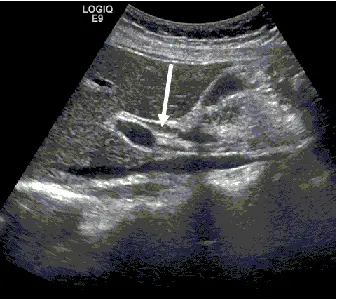

附圖為右上腹部超音波斜縱向掃描,箭號所指的構造最可能為下列何者?

- 此影像為右上腹部超音波的斜縱向掃描,主要呈現肝門區域的長軸解剖構造。

- 圖中可見三個平行的無回音(anechoic,呈現黑色)管狀構造,由淺層到深層(由前到後)排列。

- 最深處(影像最下方/解剖位置後方)口徑最大的管狀構造為下腔靜脈(inferior vena cava, IVC)。

- 位於下腔靜脈前方,具有較明顯高回音(hyperechoic,呈現白色)管壁的粗大血管為門靜脈(portal vein, PV)。

- 白色箭號所指的構造,是緊貼在門靜脈前方(腹側,靠近探頭的一側)、口徑較小的細長管狀構造。根據解剖相對位置,緊鄰門靜脈前方的管狀構造即為總膽管(common bile duct, CBD)。

在進行右上腹斜縱向掃描以觀察門靜脈長軸時,可清楚看見各血管與膽管的相對深度。根據標準解剖關係,門靜脈(PV)位於下腔靜脈(IVC)的前方;而在門靜脈的前方,則有總膽管(CBD)與肝動脈(hepatic artery)。總膽管通常與門靜脈長軸平行走向,位於其腹側(即影像的上方淺層處)。箭號明確指向門靜脈前方的細長管狀構造,故最可能為總膽管,正確答案為 (B)。